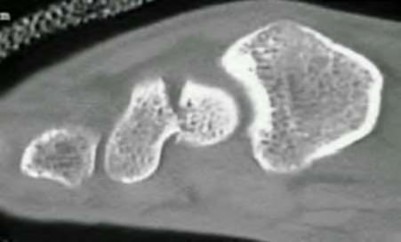

A 35-year-old woman reports wrist pain after a fall onto an outstretched hand. On exam, she has focal tenderness over the wrist snuffbox. A radiograph and CT image are shown in Figures A and B. What is the proper treatment of her injury?